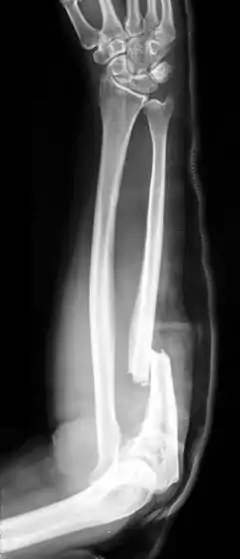

| X-ray of Monteggia fracture of right forearm | |

The Monteggia fracture is a fracture of the proximal third of the ulna with dislocation of the proximal head of the radius. It is named after Giovanni Battista Monteggia.[1][2]

There are four types (depending upon displacement of the radial head):[3]

- I - Extension type (60%) - ulna shaft angulates anteriorly (extends) and radial head dislocates anteriorly.

- II - Flexion type (15%) - ulna shaft angulates posteriorly (flexes) and radial head dislocates posteriorly.

- III - Lateral type (20%) - ulna shaft angulates laterally (bent to outside) and radial head dislocates to the side.

- IV - Combined type (5%) - ulna shaft and radial shaft are both fractured and radial head is dislocated, typically anteriorly.